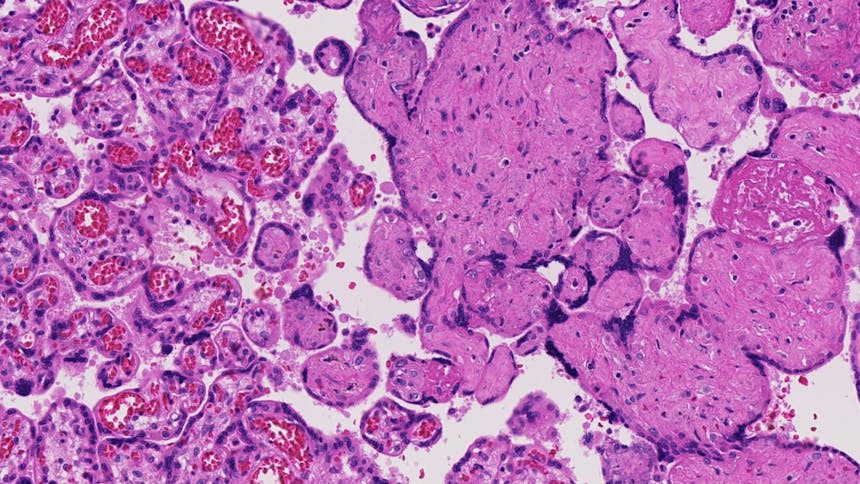

De onderzoekers hebben placenta’s van zwangerschappen waarbij het ongeboren kind een hartafwijking had vergeleken met ongecompliceerde zwangerschappen. Hiervoor hebben ze gebruik gemaakt van Dopplers waarmee ze de doorbloedingspatronen konden analyseren. Ook zijn de placenta’s door een gespecialiseerd placenta-patholoog bestudeerd onder de microscoop. De aanpak van dit onderzoek is uniek te noemen, vanwege het detailniveau waarop de placenta’s zijn geanalyseerd.